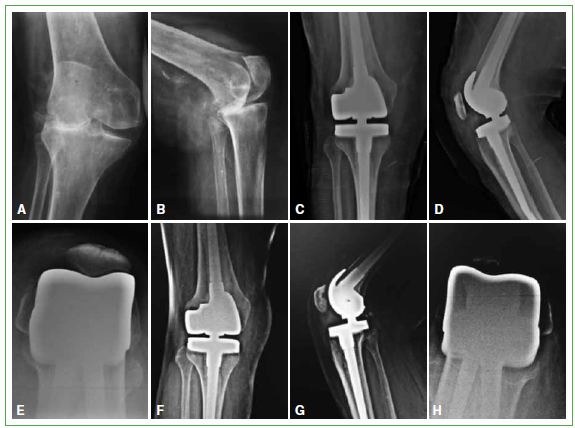

Figura 2.

Caso 17. A y B. Paciente con genu valgo severo. C-E. Radiografias posoperatorias donde se evidencia una leve lateralizacion de la rotula. F-H. Ante los sintomas por la inestabilidad rotuliana, se libero el retinaculo lateral y se implanto el componente rotuliano.

Se detectaron complicaciones en cinco de 34 protesis (14,7%). En tres pacientes (8,9%), se trato de una infeccion profunda, todas reinfecciones. Dos de los tres casos fueron tratados con limpiezas quirurgicas y tratamiento antibiotico supresor (casos 13 y 15). El restante requirio la extraccion de la protesis y la colocacion de un nuevo espaciador; sin embargo, el paciente rechazo una nueva cirugia (caso 21). Dos pacientes (5,9%) tuvieron complicaciones rotulofemorales; uno requirio, debido a reiterados episodios de luxacion rotuliana, una revision en la cual se implanto el componente rotuliano y se libero el retinaculo lateral (caso 17) (Figura 2). El paciente restante presentaba episodios de subluxacion rotuliana y, como rechazo la cirugia, fue tratado, en forma conservadora, con un plan de fortalecimiento muscular (caso 31).